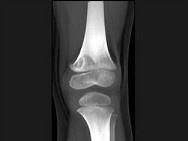

问题 男,12岁,大腿下部间歇性疼痛,劳累后加重,结合图像,最可能的诊断是?(?)

选项 A.纤维性骨皮质缺损 B.干骺端结核 C.骨样骨瘤 D.邻皮质软骨瘤 E.非骨化性纤维瘤

答案 A